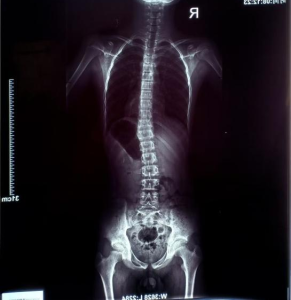

▪️ 问题类型:脊柱侧弯,Cobb角18°

▪️ 影像学报告:

康复前后对比

经过两个多月每周两次的系统性训练,目前进展成果如下:

(胸段16°到近乎0°;腰椎10°到6°)